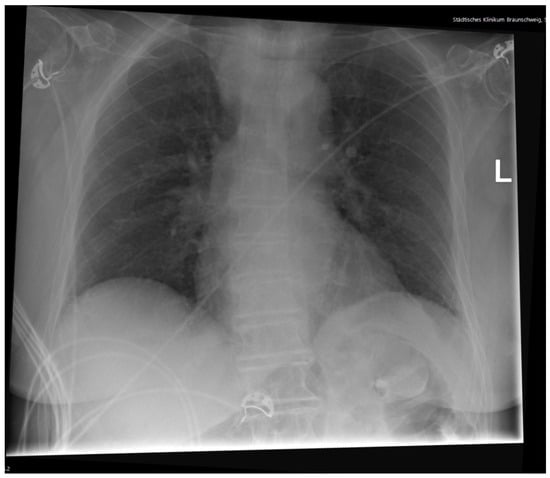

2. Case Presentation

Diagnostic Workup